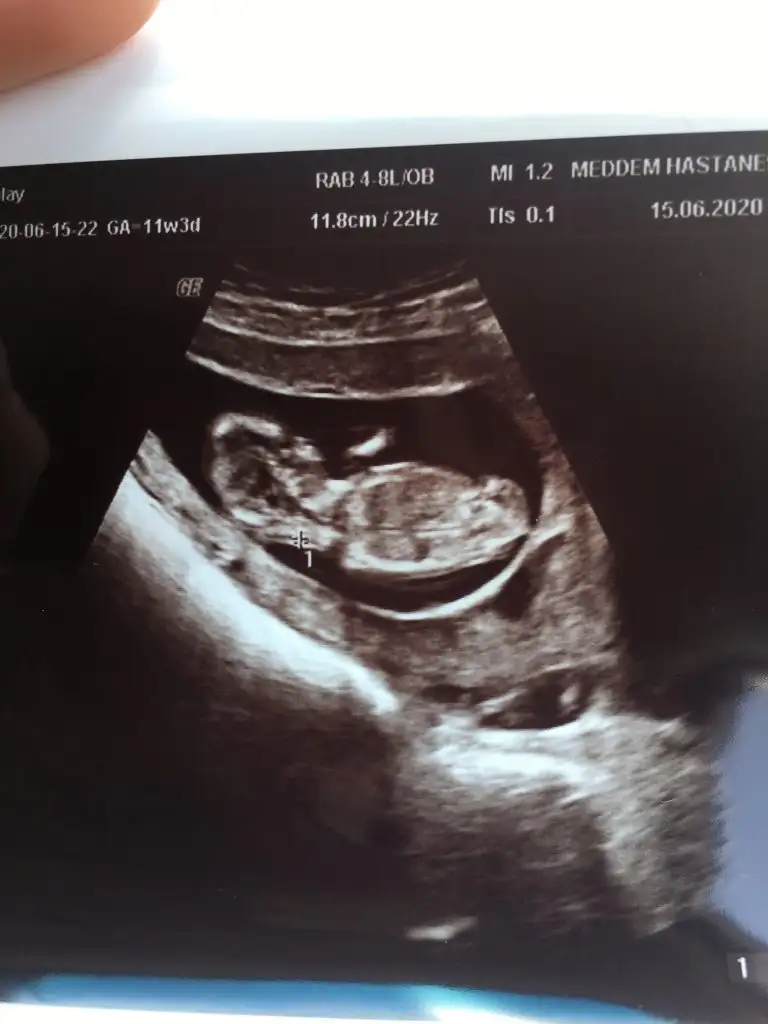

Merhaba 12 haftalık yorum yaparmısınız Eki Görüntüle 2649184

Selamlar, bu USG de benim minigime ait yorumlarsanız sevinirim

Kız gibi sanki tam net değil nubu başka usg de paylaşın